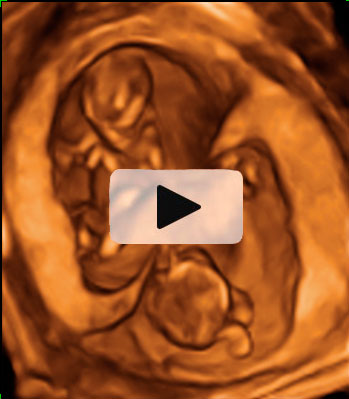

Ecografía 3D de la semana 9: Trillizos

Cada uno de los bebés crece en su bolsa amniótica

En esta ecografía en tres dimensiones (3D) se ve un embarazo de trillizos de 9 semanas. Uno de los bebés, "crece" solo dentro con una bolsa y placenta independiente. Más abajo se aprecian a otros dos bebés que también se desarrollan en bolsas independientes.

Ecografía de trillizos de 9 semanas en 3D

En la imagen se ve un embarazo de trillizos de 9 semanas tomado por un ecógrafo en tres dimensiones (3D). Se diferencia perfectamente en la parte superior de un primer bebé "en solitario" con su bolsa y placenta independientes. Una membrana gruesa le separa de sus hermanos, que se gestan con él en el útero materno. Precisamente en la parte inferior de la imagen podemos observar a los dos gemelos en bolsas también independientes, con una fina membrana de separación entre ellos.